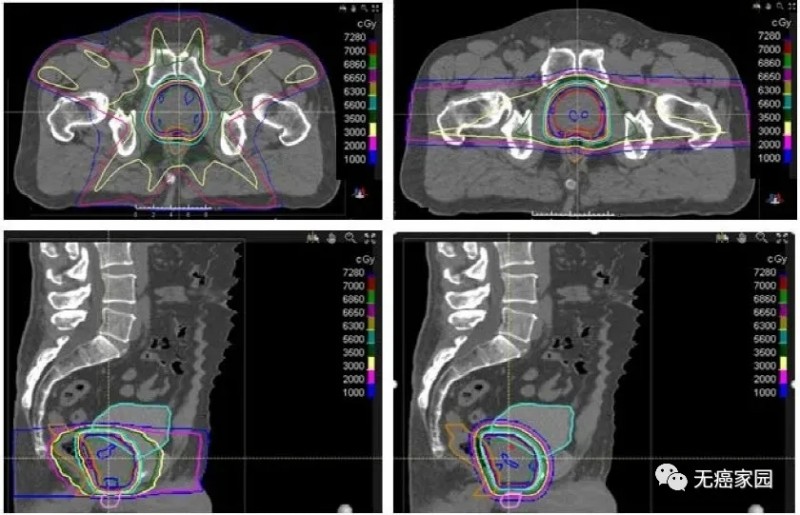

02、近距离放射治疗

近距离放射治疗是一种治疗局限性前列腺癌的技术手段,通过三维治疗计划系统的准确定位,将放射性粒子植入前列腺内,提高前列腺的局部剂量,减少直肠和膀胱的放射剂量,其疗效肯定、创伤小。

近距离放疗尤其适合于不能耐受根治性前列腺切除术的高龄前列腺癌患者。近距离放疗联合EBRT,同时加入ADT(2或3年)是治疗高危患者的常见方案。

Chera等人对15例需要盆腔淋巴结照射的高危前列腺癌患者的IMRT和DSPT计划进行了比较。临床靶区体积(CTVs)包括盆腔淋巴结、前列腺和近端精囊。前列腺和近端精囊CTV与淋巴结CTV序贯照射,分别为46 Gy,每次2 Gy。将前列腺和近端精囊CTV推量32 Gy,总剂量78 Gy。与IMRT相比,DSPT计划显著减少了接受5~40 Gy的直肠体积,从71%减少至53%。质子治疗也显著减少了过量照射的膀胱V5~V40 GyRBE,从63%减少至40%。

IMRT与DSPT前列腺癌治疗的比较。质子治疗计划减少了膀胱、直肠和阴茎球的辐射剂量,但增加了股骨头的剂量。两个计划与处方等剂量线的适形性相似。